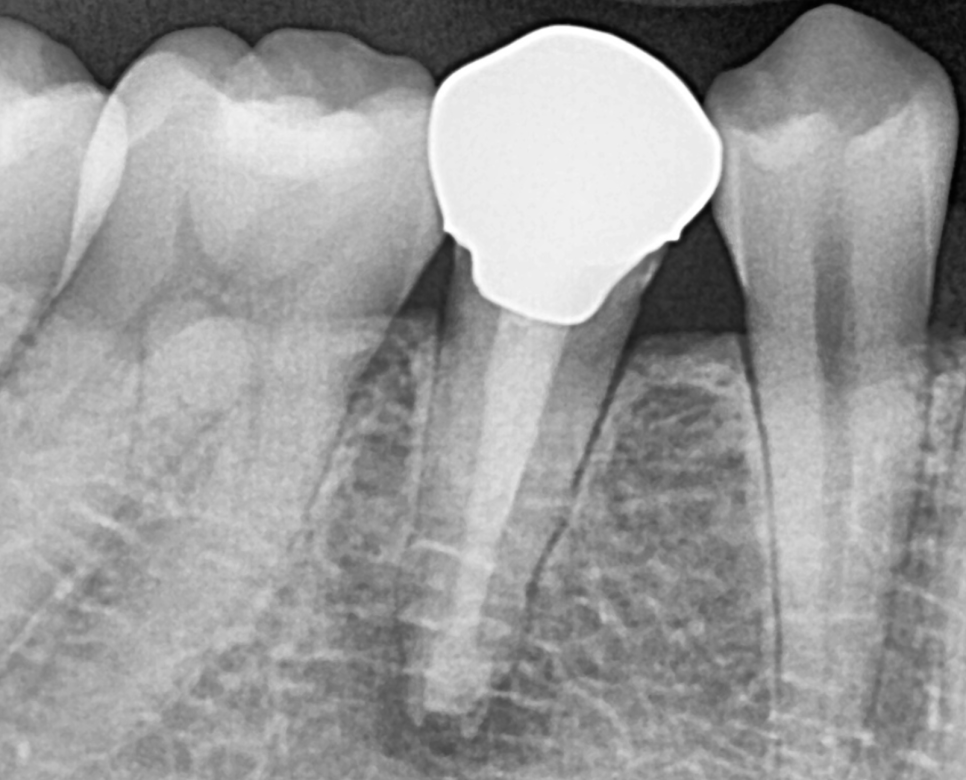

240312 뿌리 끝 염증

오늘 환자분처럼 신경치료 후 보철을 씌워주지 않으면

치아가 약해지면서

다양한 문제가 생길 수 있어요.